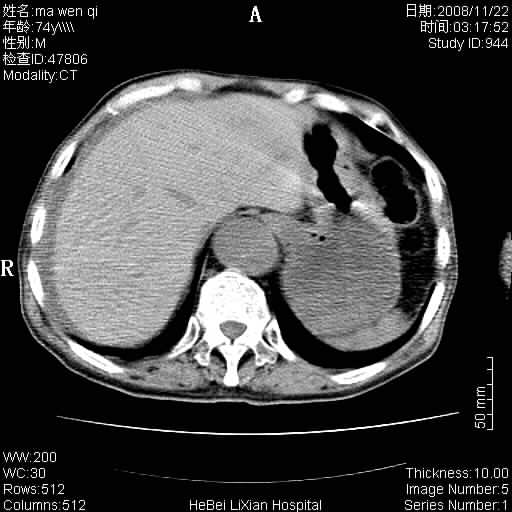

患者男 74岁.突然昏迷,休克6小时.血压70/30,头颅ct未见异常,既往体健.

补充病史,保留导尿10小时,尿袋内只有少许尿液,患者于住院后15小时后去世.

腹主动脉、双侧髂动脉夹层动脉瘤破裂出血进入腹腔。

1)考虑双侧髂动脉瘤并右侧动脉瘤破裂出血,右侧腹膜后及腹腔积血。2)双侧腹股沟疝。

1)考虑,腹主动脉、双侧髂动脉夹层动脉瘤破裂伴右侧腹膜后及腹腔积血。2)双侧腹股沟疝。

1)考虑胸、腹主动脉、双侧髂动脉瘤并右侧动脉瘤破裂出血,右侧腹膜后及腹腔积血。2)双侧腹股沟疝。